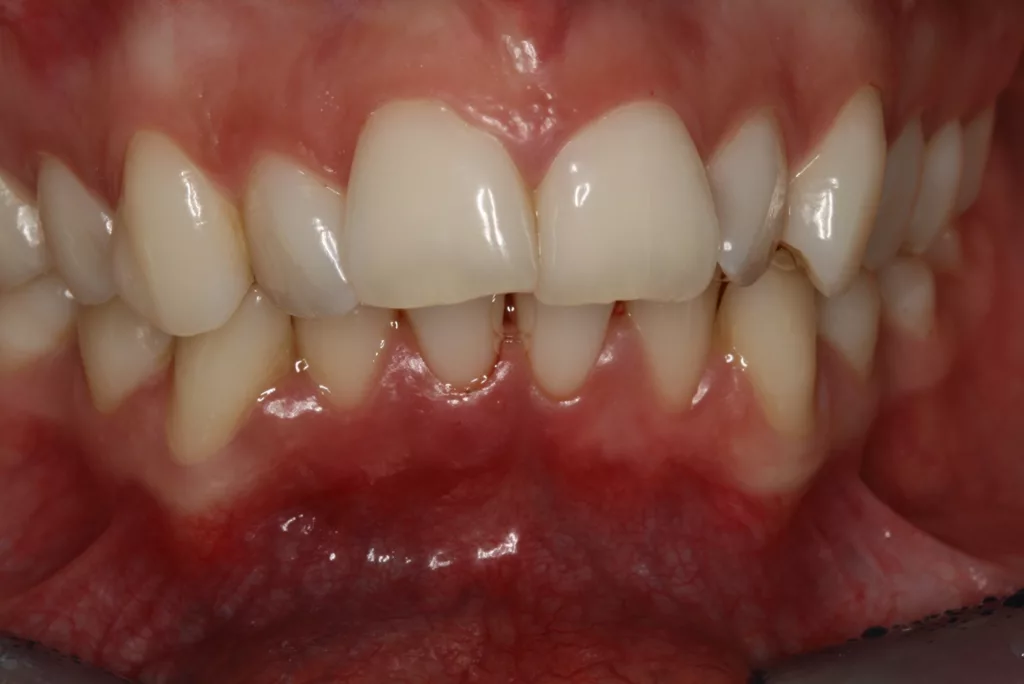

Wir sind vor mittlerweile 17 Jahren erstmals mit der Frage etwaiger Auswirkungen oraler Piercings auf den Zahnhalteapparat konfrontiert worden [10]. Eine damals 24-jährige Patientin stellte sich mit einem ungewöhnlichen Befund vor (Abb. 3a bis d). Bei sonst parodontal unauffälligen Verhältnissen mit Sondierungstiefen zwischen 2 und 3 mm, reichten die Sondierungstiefen an den Schneidezähnen im Unterkiefer bis 12 mm. Zahn 41 schmerzte und wies eine erhöhte Lockerung von Grad 2 auf. Bukkal war zudem eine Fistel mit Pusentleerung zu detektieren. Die Patientin war allgemeinmedizinisch gesund, rauchte nicht und hatte auch keinen Diabetes mellitus. Eine familiäre Prädisposition für parodontale Erkrankungen ließ sich anamnestisch nicht konstruieren. Die Mundhygiene war zwar nicht perfekt, stand aber auch in keinem Verhältnis zu ihrem dramatischen lokalen parodontalen Befund. Im Rahmen der anamnestischen Befragung, fokussiert auf ungewöhnliche Habits, berichtete die Patientin, bis vor kurzem ein Zungenpiercing getragen zu haben, dieses aber vor ca. sechs Monaten entfernt zu haben. Die Piercing-Tragedauer betrug etwa drei Jahre.

![Abb. 3a: Klinische Dokumentation einer 24-jährigen Patientin mit einer weit fortgeschrittenen lokalen parodontalen Destruktion, die mit großer Wahrscheinlichkeit durch ein Zungenpiercing hervorgerufen wurde [10]. Mit Ausnahme der Symptomatik im Unterkiefer-Frontzahnbereich wies die Patientin flache Sondierungstiefen und einzelne Regionen mit Gingivitis auf. Die Zähne reagierten positiv auf eine Sensibilitätsprobe mit Kältespray. Das Piercing war zum Zeitpunkt der Vorstellung in der Klinik bereits nicht mehr im Mund. Es wurde eine stufenweise systematische parodontale Therapie eingeleitet. Die verbliebenen und nahezu unveränderten erhöhten Son¬dierungstiefen wurden einem parodontal-chirurgischen Eingriff mit zusätzlichen, die Regenera¬tion fördernden Maßnahmen (Straumann Emdogain, Straumann, Basel, Schweiz) unterzogen. Es wurde die für diese Operationen empfohlene Schnittführung im Sinne eines Papillenerhaltungs¬lappens angewendet. Der nach der Degranulierung mit Hand- und Ultraschallinstrumenten sicht¬bare knöcherne Defekt wies eine ungünstige Morphologie für die Regeneration auf. Ein primärer Wundverschluss wurde dennoch erzielt. Diese Ansätze blieben letztendlich erfolglos und der Zahn 41 ging verloren (parodontologische Therapie gemeinsam mit Dr. L. Büttel, Basel, Schweiz).](https://dentalwelt.spitta.de/wp-content/uploads/2025/07/Abb-3a-1024x684.webp)

![Abb. 3b: Klinische Dokumentation einer 24-jährigen Patientin mit einer weit fortgeschrittenen lokalen parodontalen Destruktion, die mit großer Wahrscheinlichkeit durch ein Zungenpiercing hervorgerufen wurde [10]. Mit Ausnahme der Symptomatik im Unterkiefer-Frontzahnbereich wies die Patientin flache Sondierungstiefen und einzelne Regionen mit Gingivitis auf. Die Zähne reagierten positiv auf eine Sensibilitätsprobe mit Kältespray. Das Piercing war zum Zeitpunkt der Vorstellung in der Klinik bereits nicht mehr im Mund. Es wurde eine stufenweise systematische parodontale Therapie eingeleitet. Die verbliebenen und nahezu unveränderten erhöhten Son¬dierungstiefen wurden einem parodontal-chirurgischen Eingriff mit zusätzlichen, die Regenera¬tion fördernden Maßnahmen (Straumann Emdogain, Straumann, Basel, Schweiz) unterzogen. Es wurde die für diese Operationen empfohlene Schnittführung im Sinne eines Papillenerhaltungs¬lappens angewendet. Der nach der Degranulierung mit Hand- und Ultraschallinstrumenten sicht¬bare knöcherne Defekt wies eine ungünstige Morphologie für die Regeneration auf. Ein primärer Wundverschluss wurde dennoch erzielt. Diese Ansätze blieben letztendlich erfolglos und der Zahn 41 ging verloren (parodontologische Therapie gemeinsam mit Dr. L. Büttel, Basel, Schweiz).](https://dentalwelt.spitta.de/wp-content/uploads/2025/07/Abb-3b-1024x684.webp)

![Abb. 3c: Klinische Dokumentation einer 24-jährigen Patientin mit einer weit fortgeschrittenen lokalen parodontalen Destruktion, die mit großer Wahrscheinlichkeit durch ein Zungenpiercing hervorgerufen wurde [10]. Mit Ausnahme der Symptomatik im Unterkiefer-Frontzahnbereich wies die Patientin flache Sondierungstiefen und einzelne Regionen mit Gingivitis auf. Die Zähne reagierten positiv auf eine Sensibilitätsprobe mit Kältespray. Das Piercing war zum Zeitpunkt der Vorstellung in der Klinik bereits nicht mehr im Mund. Es wurde eine stufenweise systematische parodontale Therapie eingeleitet. Die verbliebenen und nahezu unveränderten erhöhten Son¬dierungstiefen wurden einem parodontal-chirurgischen Eingriff mit zusätzlichen, die Regenera¬tion fördernden Maßnahmen (Straumann Emdogain, Straumann, Basel, Schweiz) unterzogen. Es wurde die für diese Operationen empfohlene Schnittführung im Sinne eines Papillenerhaltungs¬lappens angewendet. Der nach der Degranulierung mit Hand- und Ultraschallinstrumenten sicht¬bare knöcherne Defekt wies eine ungünstige Morphologie für die Regeneration auf. Ein primärer Wundverschluss wurde dennoch erzielt. Diese Ansätze blieben letztendlich erfolglos und der Zahn 41 ging verloren (parodontologische Therapie gemeinsam mit Dr. L. Büttel, Basel, Schweiz).](https://dentalwelt.spitta.de/wp-content/uploads/2025/07/Abb-3c-1024x722.webp)

![Abb. 3d: Klinische Dokumentation einer 24-jährigen Patientin mit einer weit fortgeschrittenen lokalen parodontalen Destruktion, die mit großer Wahrscheinlichkeit durch ein Zungenpiercing hervorgerufen wurde [10]. Mit Ausnahme der Symptomatik im Unterkiefer-Frontzahnbereich wies die Patientin flache Sondierungstiefen und einzelne Regionen mit Gingivitis auf. Die Zähne reagierten positiv auf eine Sensibilitätsprobe mit Kältespray. Das Piercing war zum Zeitpunkt der Vorstellung in der Klinik bereits nicht mehr im Mund. Es wurde eine stufenweise systematische parodontale Therapie eingeleitet. Die verbliebenen und nahezu unveränderten erhöhten Son¬dierungstiefen wurden einem parodontal-chirurgischen Eingriff mit zusätzlichen, die Regenera¬tion fördernden Maßnahmen (Straumann Emdogain, Straumann, Basel, Schweiz) unterzogen. Es wurde die für diese Operationen empfohlene Schnittführung im Sinne eines Papillenerhaltungs¬lappens angewendet. Der nach der Degranulierung mit Hand- und Ultraschallinstrumenten sicht¬bare knöcherne Defekt wies eine ungünstige Morphologie für die Regeneration auf. Ein primärer Wundverschluss wurde dennoch erzielt. Diese Ansätze blieben letztendlich erfolglos und der Zahn 41 ging verloren (parodontologische Therapie gemeinsam mit Dr. L. Büttel, Basel, Schweiz).](https://dentalwelt.spitta.de/wp-content/uploads/2025/07/Abb-3d-1024x665.webp)